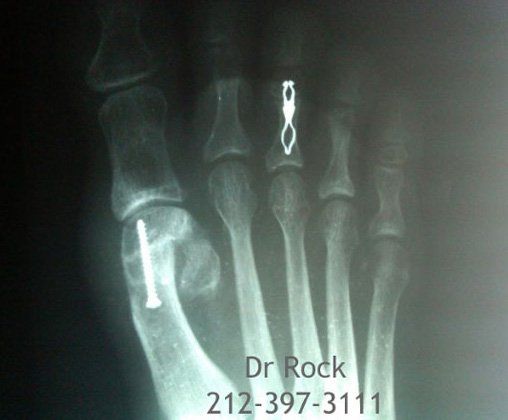

Take a look at our x-ray pictures of our recent footwork and see how your feet can benefit.

Whether you want to improve the look of your feet or need to relieve pain,

you can find out the best option for you with our FREE phone consultation.